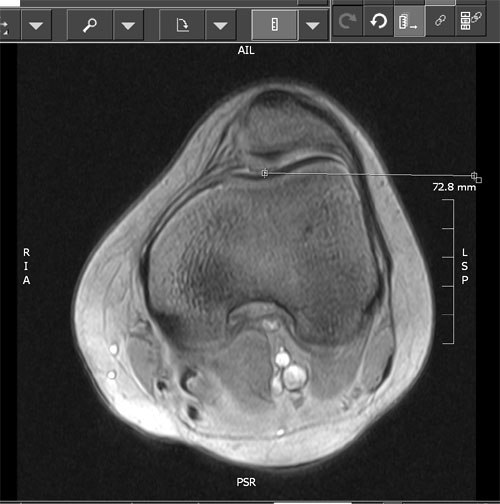

The patellotrochlear index laves på basis af MR skanning:

Index: BL(P)/BL(T)*100= index: <12,5%= Patella alta. >50% = Patella infera